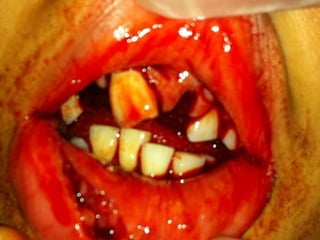

Swollen floor of mouth, elevated tongue

Cellulitis of bilateral submandibular spaces

and sublingual space

Direct connection to parapharyngeal space

Airway at risk!